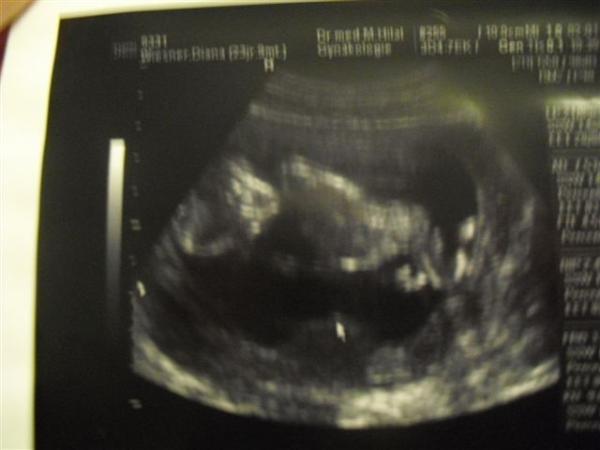

Hi Leute, wollte euch mal ein Bild von unserem Kleinen zeigen:-) Hoffe ihr könnt was erkennen...links Köpfchen, dann Bäuchlein und rechts Beinchen:-) LG Maja

Dein Würmchen hat es sich aber auch schön bequem gemacht... man kann es gut erkennen...